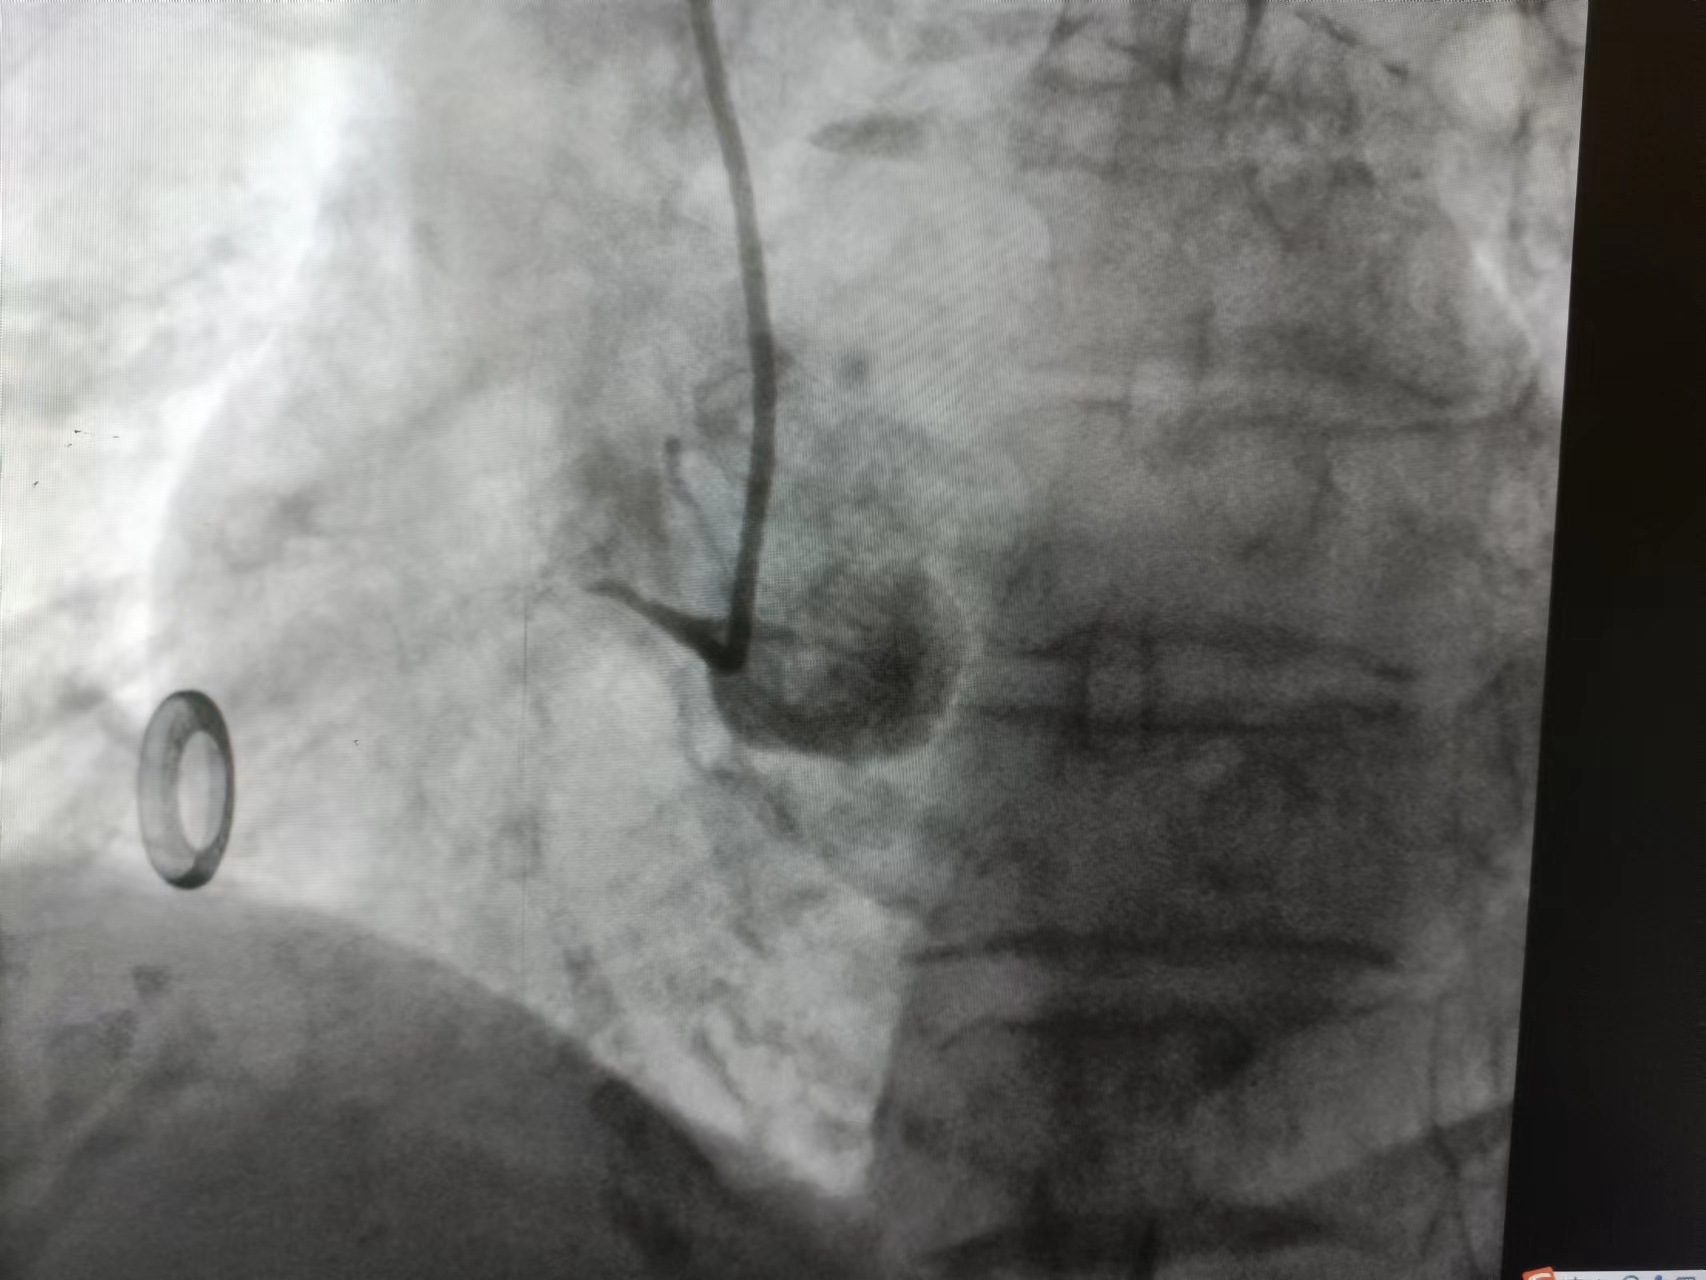

![]() ![]() ![]() 术前冠脉造影

![]() 术后冠脉造影

植入支架发生慢血流

血流恢复